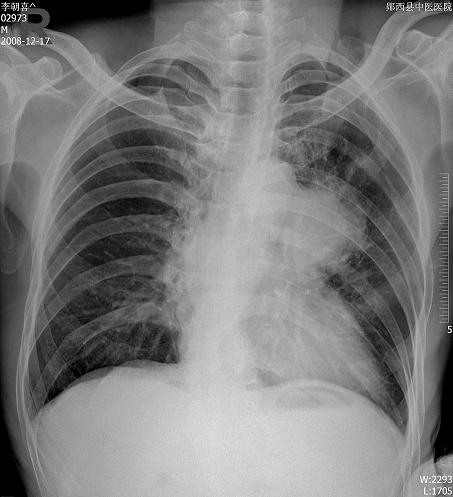

m ,59y,08年12月诊断左侧中央型肺癌,今日复查块影不明显,患者不愿再作ct.

08年cr及ct图像: